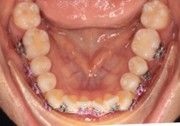

The IOS Mini Cinch Back Plier demonstrated superior control and a significantly reduced risk of bracket debonding and wire deformation compared to the regular Hammerhead plier from a different brand. Wire bends achieved with the IOS Mini Cinch Back Plier maintained integrity even under high-torque activation. The following images illustrate key differences in bend quality, wire distortion, and proximity to the bracket between the IOS Mini Cinch Back Plier and the conventional Hammerhead plier.